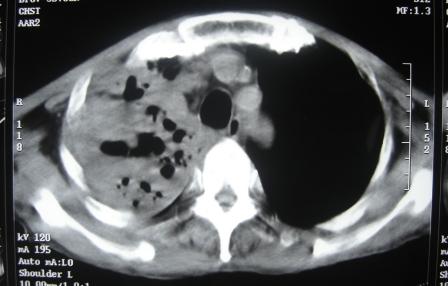

xx 男 63岁 发热 家属描述有时高热 有时低热 抗酸杆菌阴性 于2月21号 胸片及ct

3月10号复查